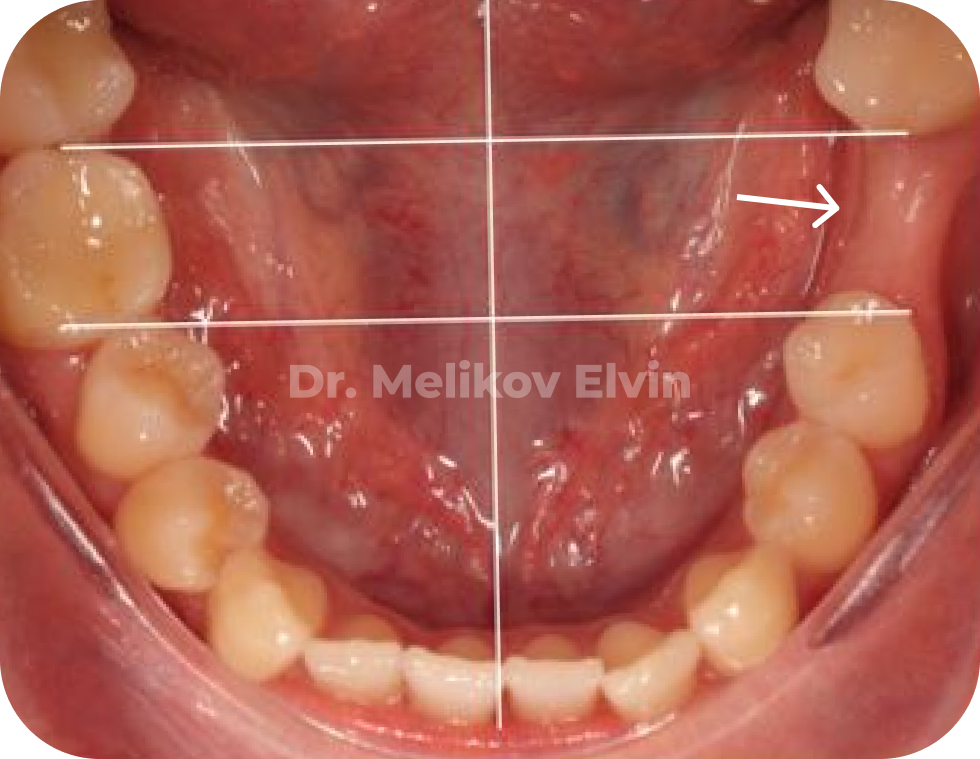

Клинический случай

🔹 Пациентка обратилась с целью стоматологической реабилитации с использованием дентальных имплантатов.

🔹 Жалобы на отсутствие зуба 1.5 и 3.6, которые были потеряны вследствие осложнения кариеса.

❗️Выявлена аномалия прикуса.